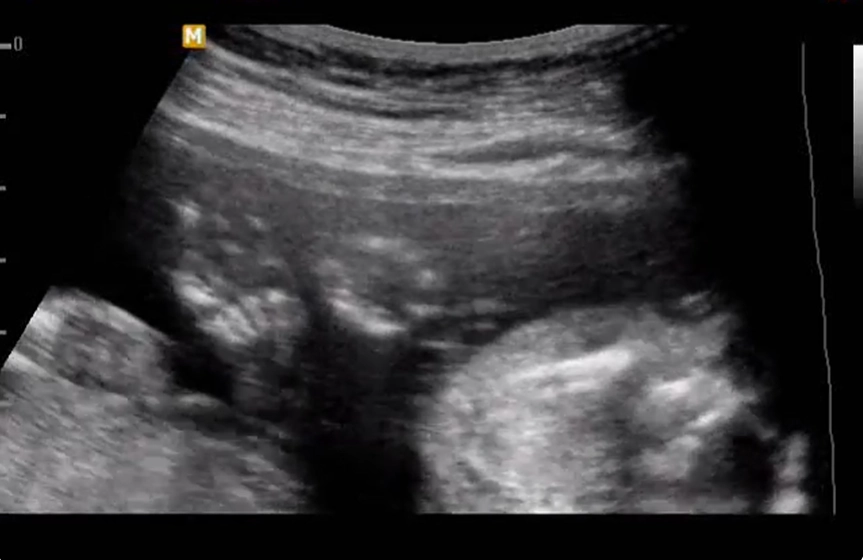

Bàn chân gót lồi- Bàn chân ngựa gỗ (Rocker-Bottom Foot)